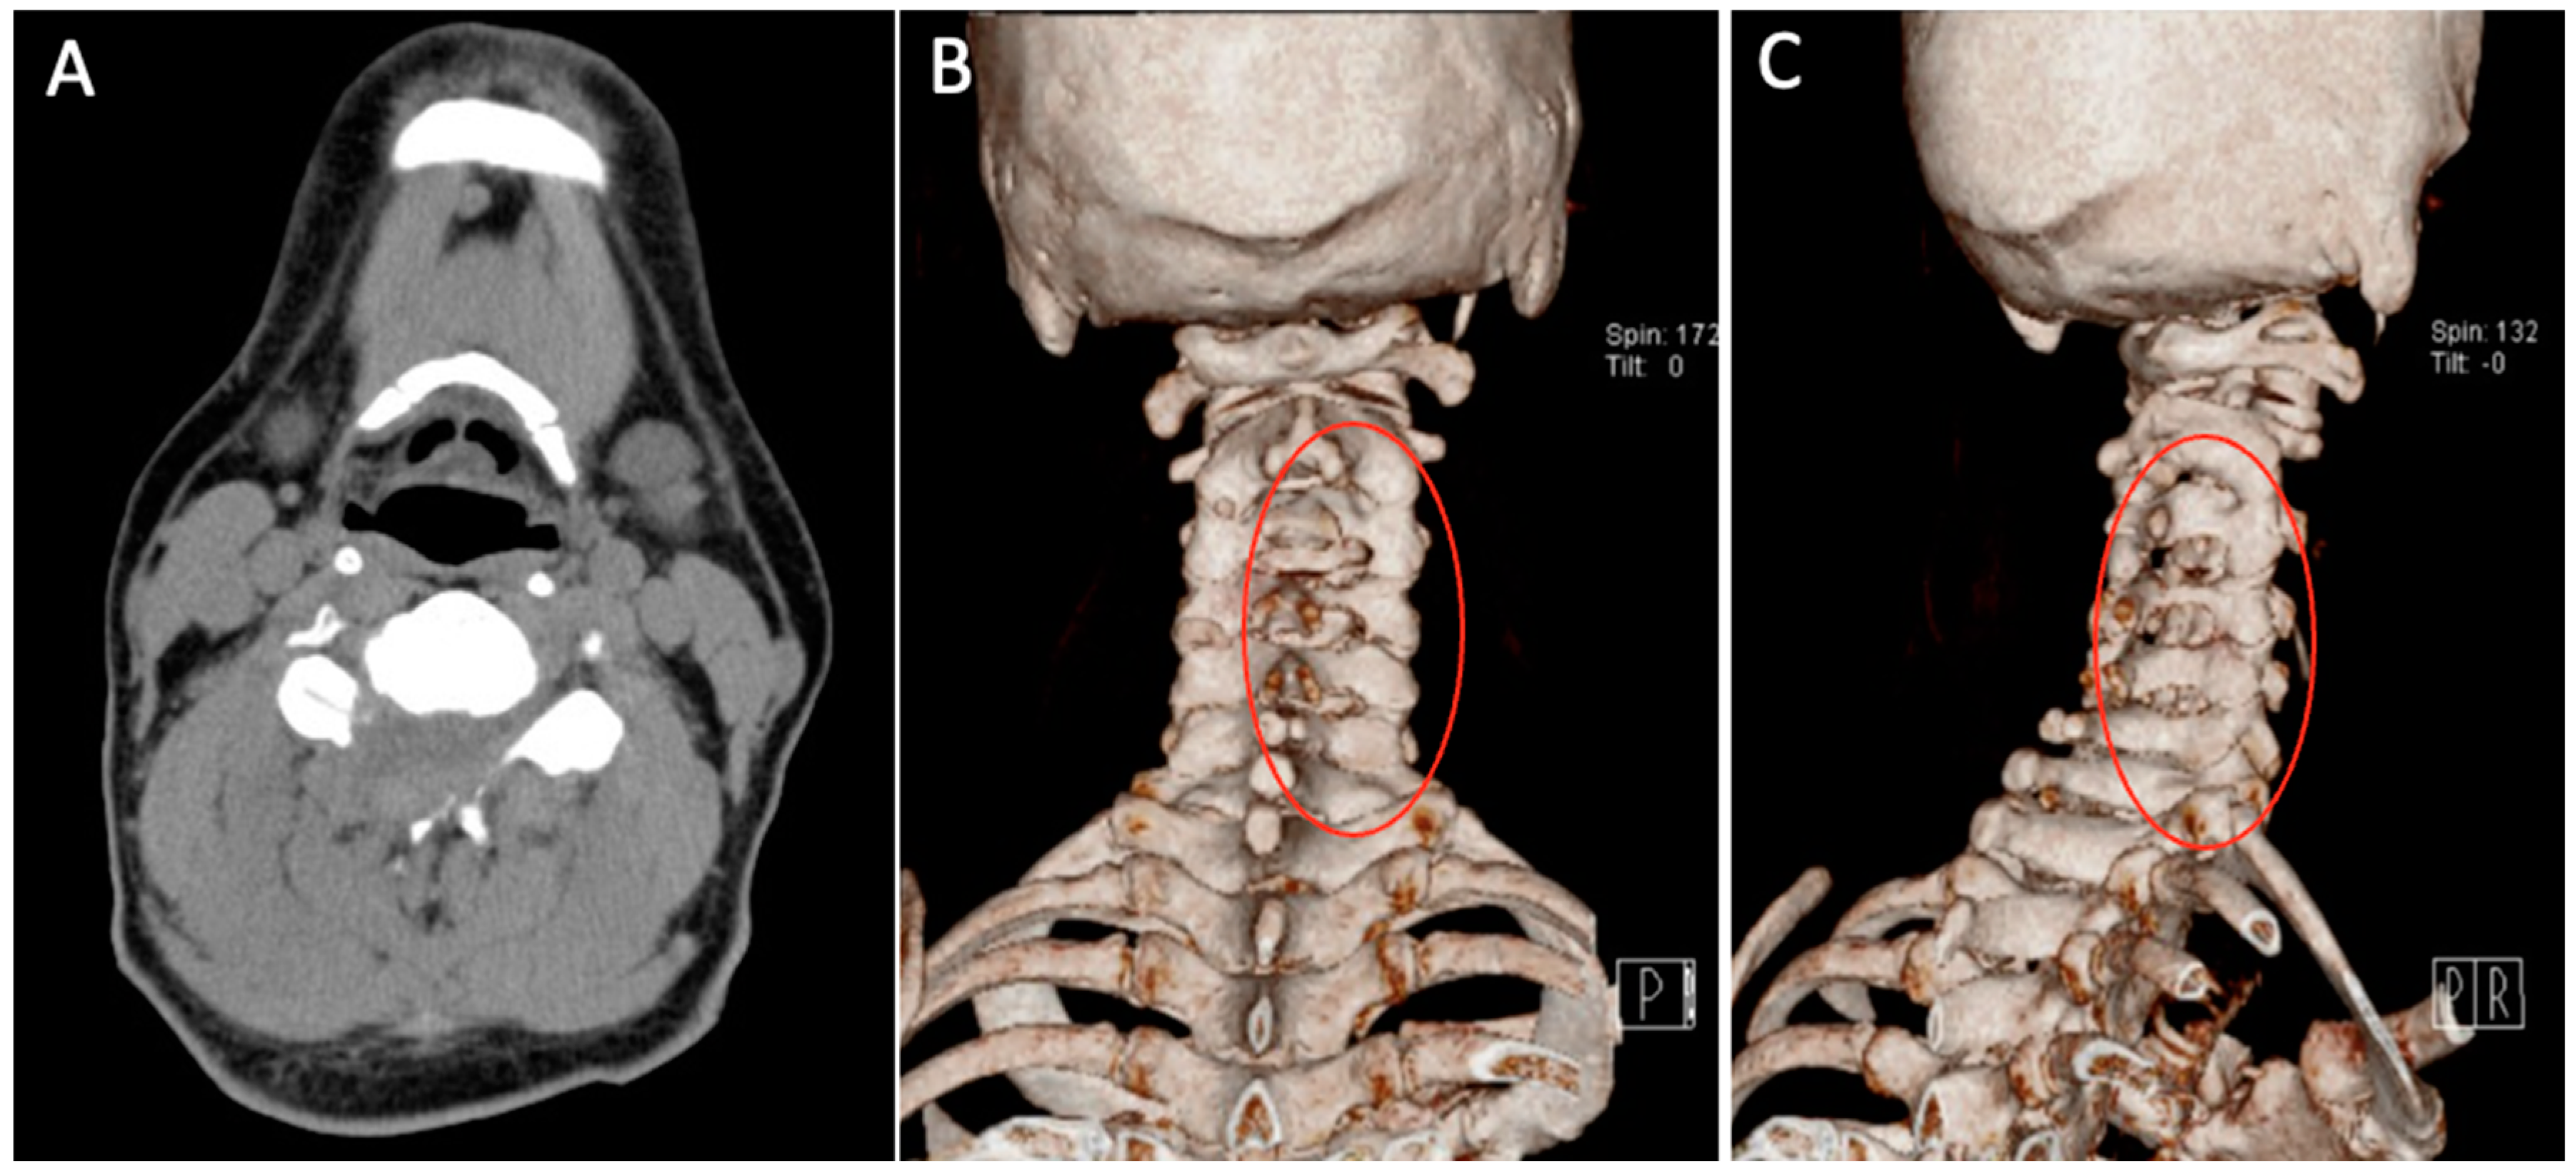

Patient underwent C3-C6 CE-ULFBD on 8 August 2020. The operation time was 182 min, and blood loss was 12 mL. There were no neurologic complications during operation under the monitoring of MEP (motor-evoked potential) and SSEP (somatosensory-evoked potential). The postoperative radiograph and CT scan revealed successful and substantial decompression of both the foraminotomy and laminotomy procedures (Figure 10). The patients were then discharged on postoperative day 3. At 8-month follow-up, the VAS score for neck discomfort has notably decreased from 7 to 0, while a similar improvement has been noted in the VAS score for hand discomfort, which decreased from 5 to 0. Additionally, there has been a considerable enhancement in lower limb motor strength without temporary lower limb weakness. Furthermore, the modified Japanese Orthopedic Association (mJOA) scores have exhibited positive progress, having risen to 17, reflecting an overall improvement in the patient’s condition.

Figure 10. Postoperative axial CT images (A) and CT 3-dimensional reconstruction (B,C). CT = computed tomography. The areas marked by red circles indicate the parts of the cervical spine that were decompressed during surgery.